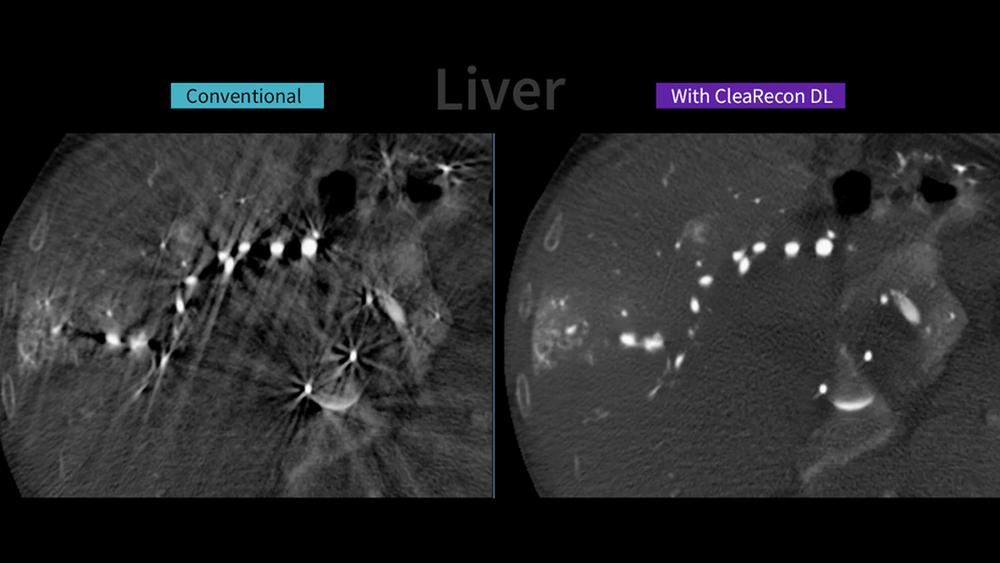

GE HealthCare ha annunciato il lancio di CleaRecon DL, una tecnologia basata su un algoritmo di deep learning progettata per migliorare la qualità delle immagini ottenute con la tomografia computerizzata a fascio conico (CBCT). Questa soluzione, alimentata da intelligenza artificiale (AI), è studiata per eliminare gli artefatti a striature causati dalla pulsatilità del flusso ematico arterioso e dalle variazioni nella distribuzione del mezzo di contrasto durante le acquisizioni CBCT nelle procedure interventistiche epatiche, prostatiche, neurovascolari e di riparazione endovascolare dell’aorta. CleaRecon DL ha recentemente ottenuto la certificazione 510(k) della FDA statunitense e la marcatura CE, ed è disponibile per l’utilizzo sulla piattaforma Allia™.[¹]

La CBCT viene utilizzata nelle sale interventistiche per fornire immagini in sezione trasversale durante le procedure. Tuttavia, la qualità delle immagini ricostruite può risultare compromessa da artefatti dovuti alla pulsazione dei vasi, che ne riducono nitidezza e accuratezza. Queste limitazioni possono minare la fiducia nell’interpretazione delle immagini CBCT e ostacolarne l’impiego routinario nella pratica clinica.[²] Nonostante tali criticità, la CBCT rimane essenziale per la sua capacità di offrire una visualizzazione dettagliata dell’anatomia, migliorando la precisione degli interventi.

Il deep learning è oggi la tecnica di machine learning più avanzata per l’elaborazione delle immagini: un’intelligenza artificiale addestrata per generare dati ed eseguire compiti specifici.[³] CleaRecon DL utilizza algoritmi di deep learning per generare immagini CBCT più nitide e accurate, offrendo ai professionisti sanitari un supporto concreto nel processo decisionale clinico e contribuendo a migliorare la qualità dell’assistenza.

Nei test di validazione clinica, un recente studio ha evidenziato che, nel 98% dei casi, le immagini CBCT ricostruite con CleaRecon DL risultano più chiare rispetto a quelle convenzionali, mentre nel 94% dei casi è stato riportato un aumento della sicurezza diagnostica da parte dei medici.[⁴]